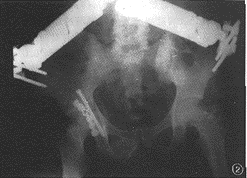

本组2例多发伤患者,经牵引6周后改行手术治疗,术中发现骨折处解剖对位困难,出血活跃。术后1例患者髋关节周围形成严重HO(图1),另1例患者发生股骨头缺血性坏死。因此,手术时机应掌握在伤后3~7d为宜,最迟也不应超过伤后3周。Wright等[2]在一组疗效对比研究中发现,伤后1周之内完成手术的患者,其预后明显优于延迟治疗组患者,前者的HHS平均为81分,而后者仅为64分。这与我们的研究结果相似。临床上急诊手术的适应证被界定为:股骨头后脱位闭合复位失败,后壁骨折阻挡股骨头还纳或复位后难以取得并保持Mose同心圆对位,手法复位后出现坐骨神经麻痹症状,开放性髋臼骨折或伴发血管损伤者。本组未行急诊手术的12例患者中有7例发生了股骨头坏死。

图1陈旧性髋臼骨折术后发生异位骨化